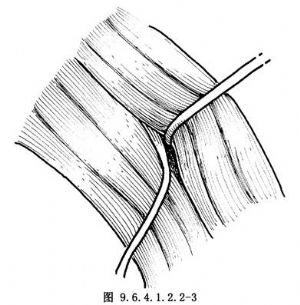

9.3 3.製備神經肌蒂

遊離胸鎖乳突肌前緣並牽向後,找到舌下神經襻至肩胛舌骨肌的分支(圖9.6.4.1.2.2-2),沿該分支向下分離至神經實際進入肌肉處,切取2~3mm3大小肌塊,連同神經一起保護備用(圖9.6.4.1.2.2-3,9.6.4.1.2.2-4)。